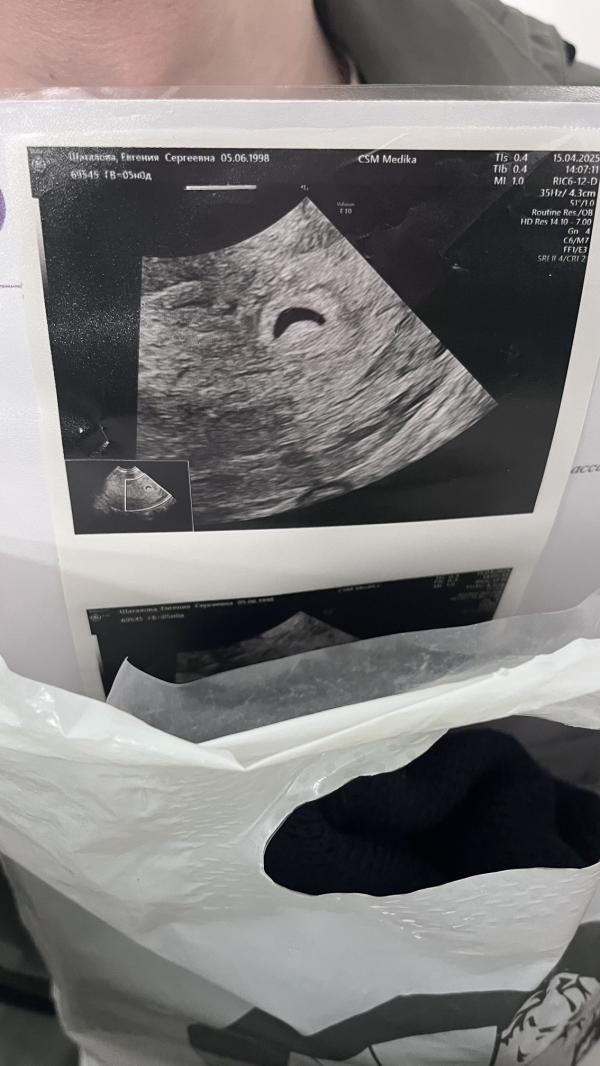

Всем привет! У кого нибудь было плодное яйцо изначально на первых неделях формой типа месяца ?

У меня 5 недель и оно как месяц, сказали должен быть круглое, врач говорит может такая особенность или то что еще ранний срок мол

Сказал на контрольное узи через 10 дней приходить

Но говорит круглое должно быть, хотя чат gpt пишет что ничего страшного выправится 🙈